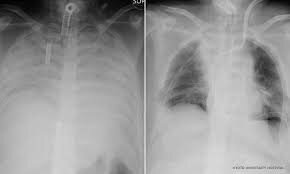

به گزارش ایسنا، یک زن ژاپنی که ریههای او به دلیل خطر ابتلا به بیماری کووید-۱۹ دچار آسیب جدی شده بود، تحت عمل پیوند ریه قرار گرفت. برای اولین بار است پیوند ریه از یک اهدا کننده زنده روی بیمار بهبود یافته مبتلا به کووید-۱۹ انجام گرفته است.

پزشکان ژاپنی اظهار کردند: در این عمل جراحی ۱۱ ساعته که توسط ۳۰ تیم پزشکی انجام گرفت، بافت ریه از همسر و پسر این بیمار به او پیوند شد.

بیماری کووید-۱۹ میتواند عامل آسیب دیدن ریه در برخی از بیماران شود و مردم سراسر جهان به عنوان بخشی از روند بهبود بیماری تحت پیوند ریه قرار میگیرند اما مسئولان بیمارستان کیوتو اعلام کردند که این جراحی پیوند، اولین مورد بوده که بافت ریه از اهدا کننده زنده به بیمار مبتلا به کووید-۱۹ پیوند زده شده است.